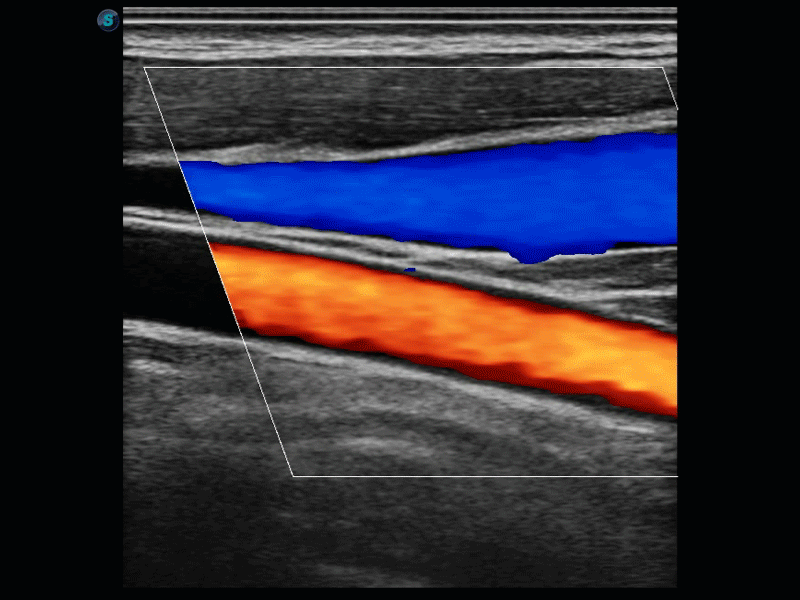

開立醫(yī)療通過不斷的技術(shù)創(chuàng)新,為大眾的生命健康提供持續(xù)關(guān)愛。P12 Plus采用全新一代超聲成像平臺(tái),新平臺(tái)旨在將真實(shí)還原組織解剖結(jié)構(gòu)作為首要目標(biāo)。平臺(tái)采用全新集成化硬件模塊,搭載新一代芯片,系統(tǒng)性能得到大幅提升,為您的診斷提供了豐富的臨床信息。優(yōu)異的圖像表現(xiàn),豐富的探頭配置,全面的應(yīng)用功能,為您日常診斷提供了可靠的助手。

P12 Plus

彩色多普勒超聲診斷系統(tǒng)